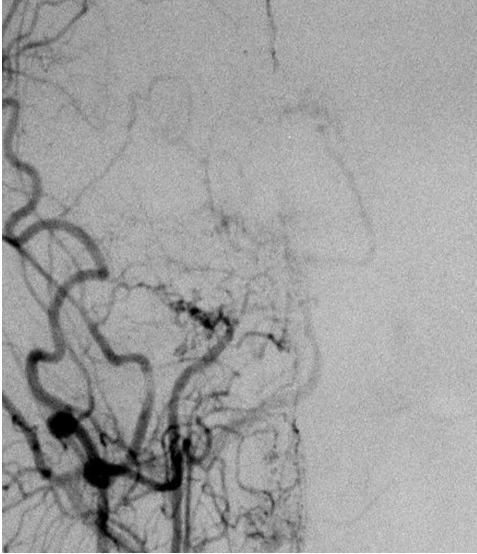

The cerebral angiogram shows abnormal, dilated, and irregular collateral vessels (_____ appearance) which are characteristic of _____ disease